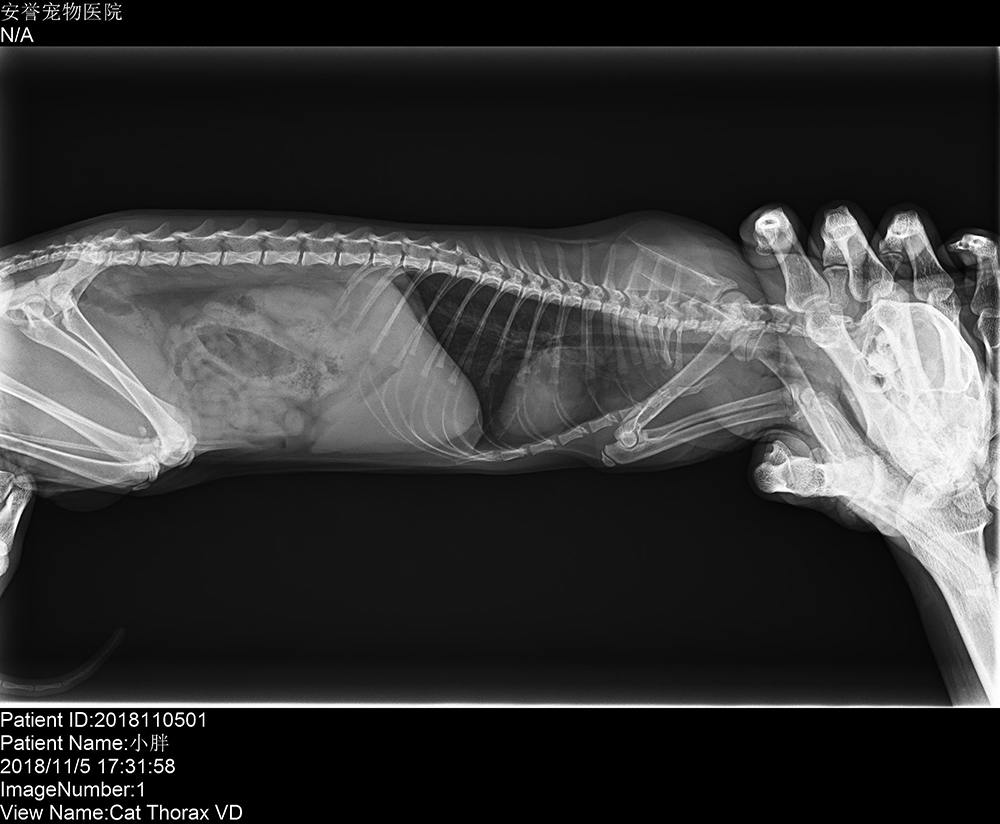

廣州安安醫(yī)寵安譽寵物(wù)醫(yī)院 2018/11/8 上(shàng)一(yī)篇: 沒有(yǒu)了(le) 下(xià)一(yī)篇: 深圳安安醫(yī)寵前海(hǎi)分(fēn)院